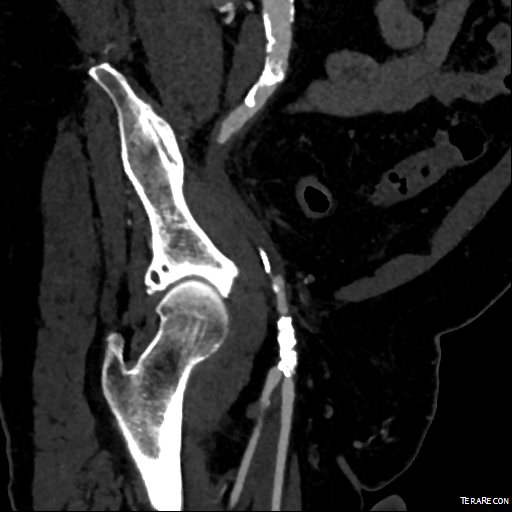

This patient presents with lifestyle limiting claudication and an absent right femoral pulse. ABI is moderately reduced on the right to 0.57, and he had no rest pain. CTA at our clinic revealed an occluded EIA bracketed by severely calcified and nearly occlusive plaque of the common iliac artery (CIA) and common femoral artery (CFA).